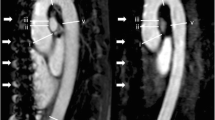

A 34-year-old male patient with aortic coarctation. Oblique sagittal view of unenhanced 3D SSFP MRA (a) and CE-MRA (b) demonstrate the significant focal stenosis of the distal transverse arch consistent with aortic coarctation (a and b, arrow). Three-dimensional volume rendered image also shows the coarctation (c, arrow)

A 51-year-old male patient, status post-surgical repair of type I dissection with residual intimal flap in the arch and descending aorta. Sagittal oblique image from non-contrast 3D SSFP MRA (a) and corresponding sagittal oblique image from CE-MRA (b) demonstrate the ascending aortic surgical graft (a and b, small thin arrow), anterior true lumen (a and b, small arrow), posterior false lumen (a and b, arrowhead), aneurysmal dilatation of the distal transverse arch, and the residual low signal intimal flap (a and b, large arrow). Mural thrombus in the false lumen of the aortic arch (a and b, large thin arrow) is better appreciated on non-contrast SSFP MRA